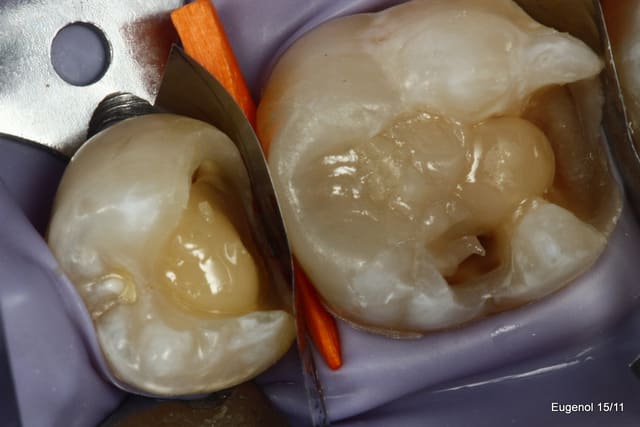

un truc que je fais souvent, quand je monte deux compo volumineux en contact, je monte le plus gros et difficile sans matrice et comme ça j'ai accès a la marge, et je peux donner une jolie forme galbée proximale

puis je monte le suivant avec une seule matrice...

plus facile je trouve d'avoir le point de contact

Je propose cette approche dans les cas particulier où l'on a deux box volumineux face à face. Il est difficile dans ses cas d'obtenir un point de contact efficace.

Je le fais quand je peux facilement avoir accès à la spatule à toute la face proximale